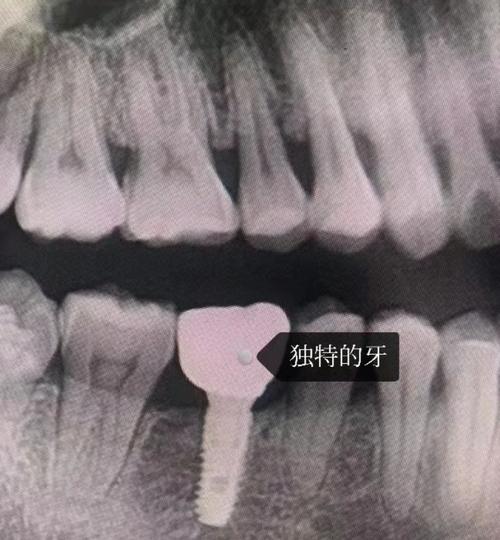

- CBCT(锥形束CT):可3D呈现口腔骨量、神经血管位置,精准设计种植方案;

- 种植导航系统:术中实时引导种植体植入角度、深度,降低误差(误差可控制在0.1mm内)。